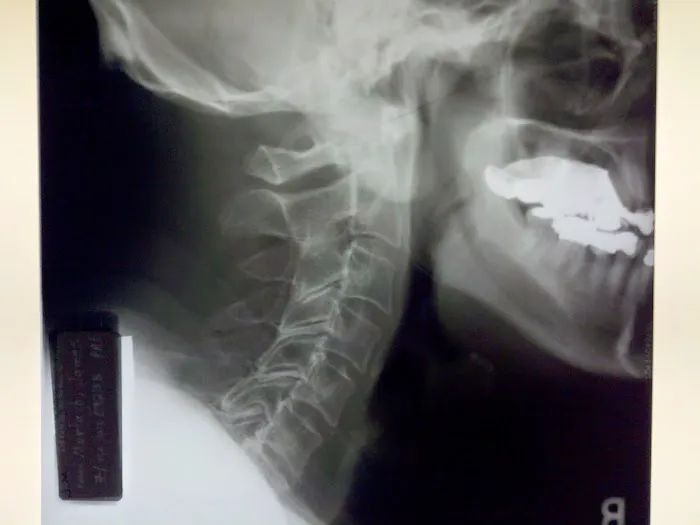

Chiropractic care is a healthcare profession focused on the diagnosis, treatment, and prevention of musculoskeletal disorders, with a primary emphasis on the spine and its impact on the nervous system. While traditional chiropractic often involves manual adjustments that may produce joint cavitation sounds (cracks), specialized approaches like Atlas Orthogonal chiropractic offer a distinctly different experience. This technique focuses on the Atlas vertebra (C1), the uppermost bone in the spine, and its relationship with the skull and the rest of the spinal column. Even a slight misalignment in this crucial area can impact the entire nervous system, leading to widespread issues. Dr. Thomas at Atlas Orthogonal Chiropractic, LLC, utilizes this highly precise, gentle method to realign the Atlas, often without any cracking. This precise adjustment aims to restore proper communication between the brain and body, alleviate pressure on nerves, and allow the body to heal naturally. This approach, combined with other therapeutic modalities, offers a powerful, non-invasive path to relief and long-term wellness.

Atlas Orthogonal Adjustments: This is the cornerstone and specialty of the practice. Utilizing a precise, gentle instrument, Dr. Thomas makes subtle adjustments to the Atlas vertebra (C1), without any twisting, popping, or cracking. This method aims to restore proper alignment of the head and neck, alleviating nerve pressure and allowing the body's natural healing processes to take over.